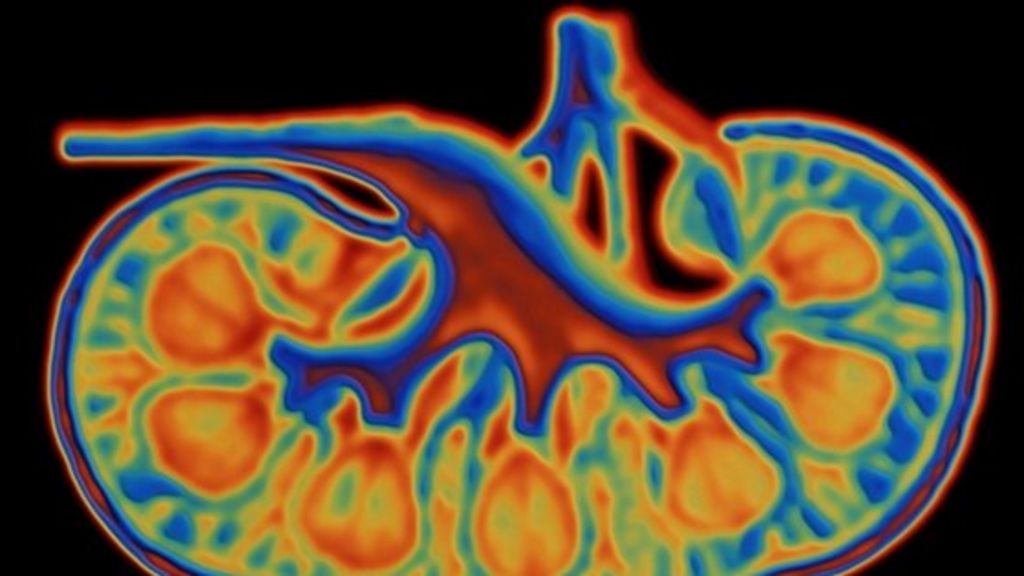

Artificial Human Kidney . The artificial kidney is designed to work like the natural. will the artificial kidney work as well as a human kidney? in this review, we discuss the characteristics of an ideal artificial kidney, the challenges of developing such a. the ideal rrt must mimic the complex structure of the human kidney. could implantable artificial kidneys end the need for dialysis? scientists at uc san francisco are working on a new approach to treating kidney failure that could one day free people from needing. portable, wearable and implantable artificial kidney systems require compact and efficient dialysate. Highly engineered mechanical structures could radically improve the quality of life for people with chronic kidney disease.